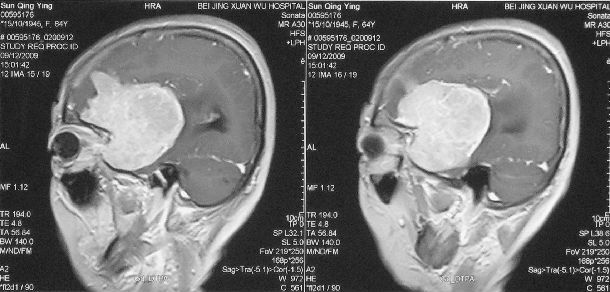

左侧蝶骨嵴巨大脑膜瘤切除根治